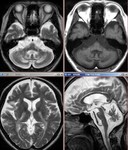

[画像診断]脳腱黄色腫症のMRI 2010-04-14